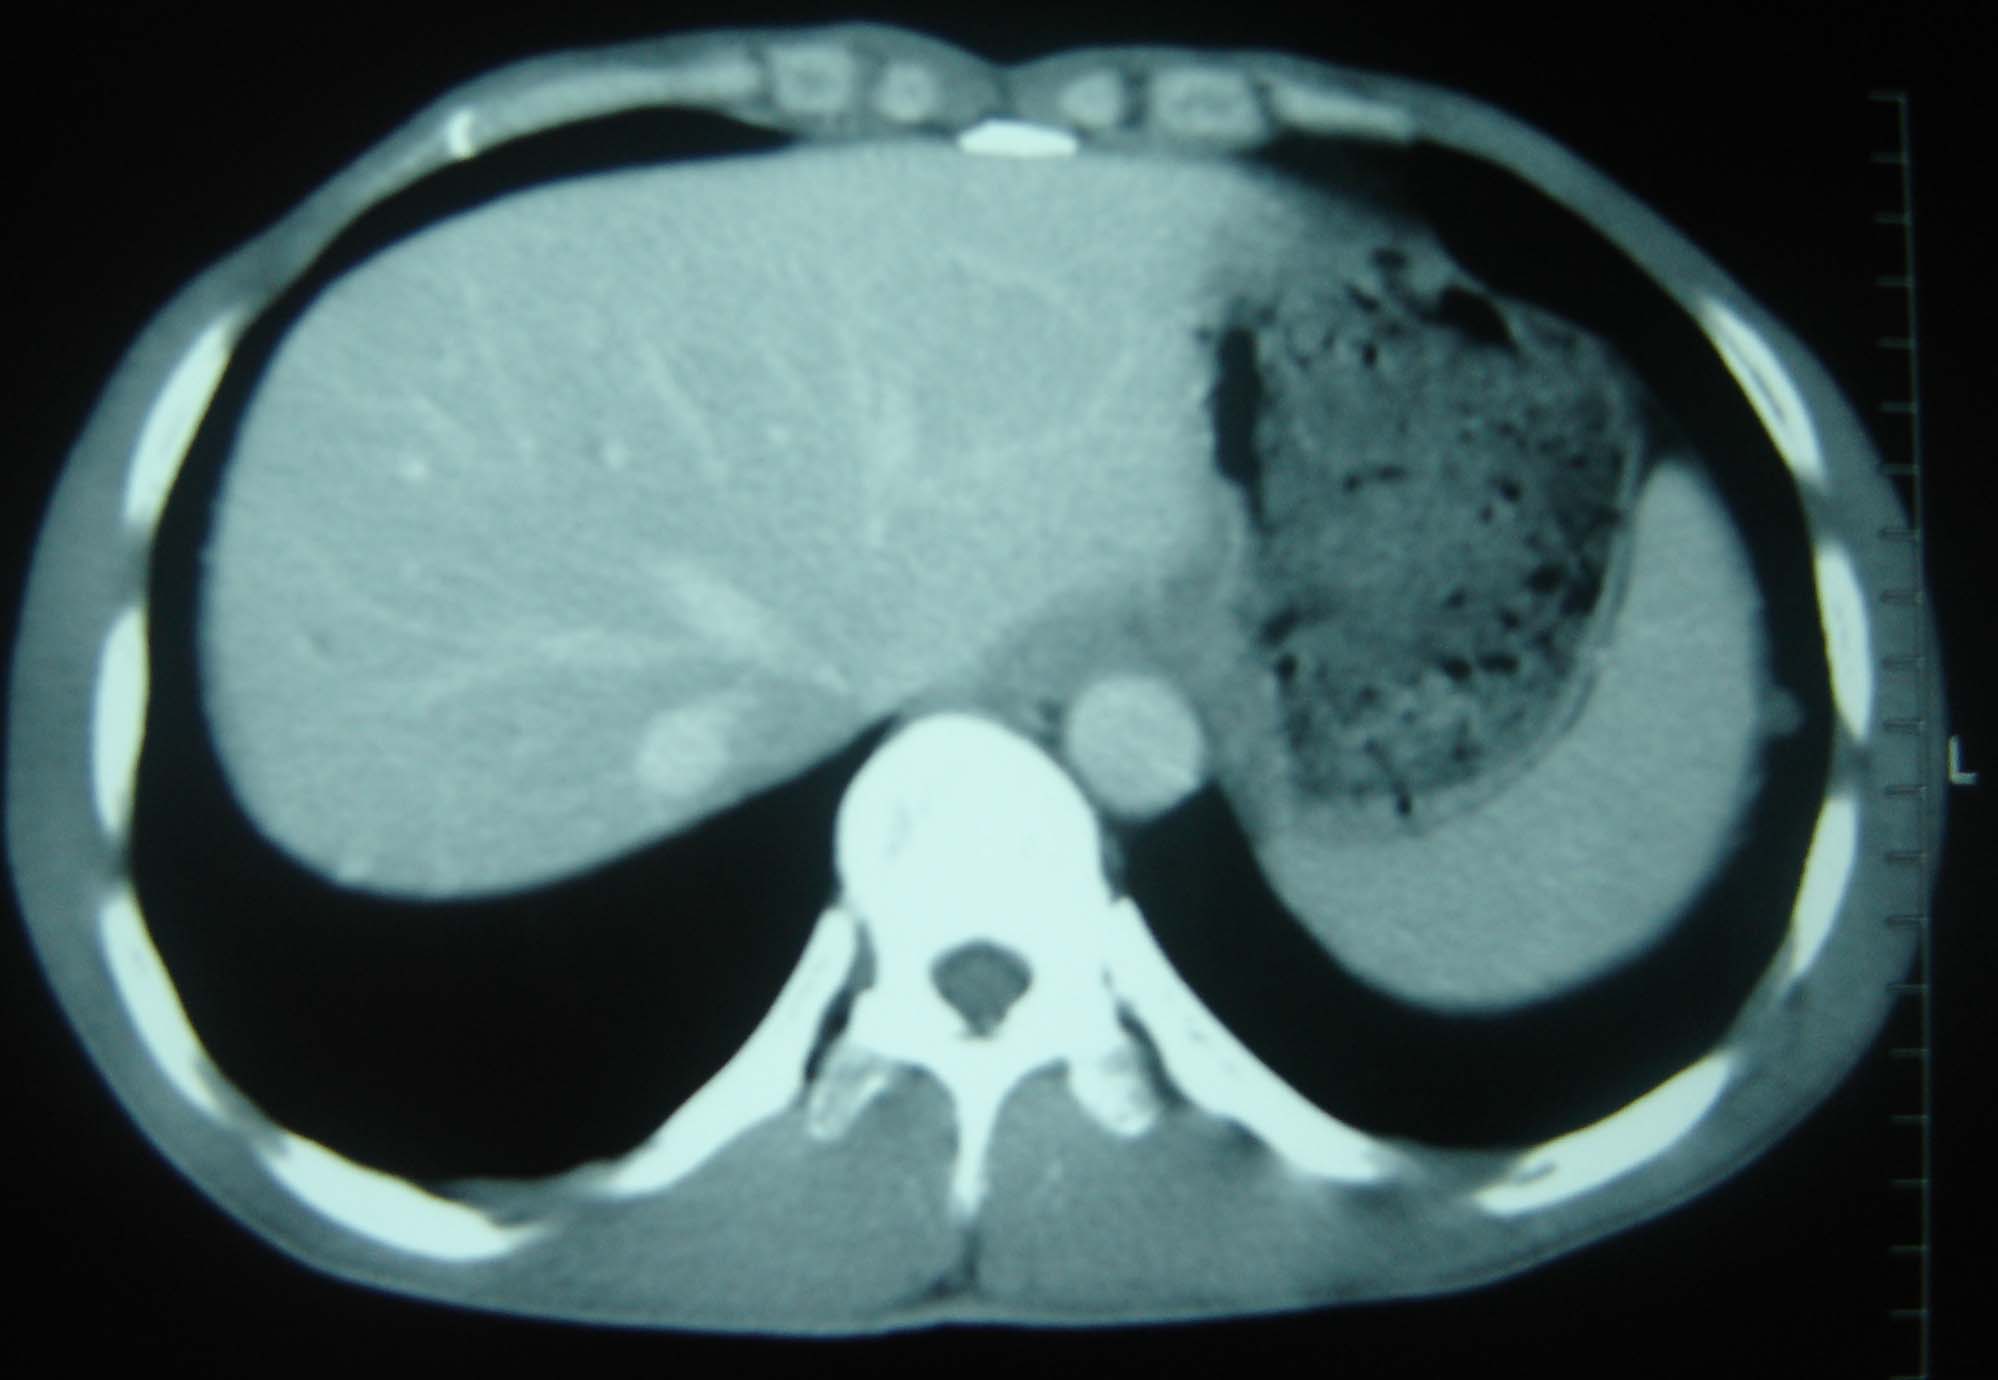

男 、43岁,咳嗽胸痛,装修工,平时接触粉尘较多,有吸烟史10多年,纤维支气管镜检查未发现异常,胃镜、腹部b超检查亦未发现异常,颈部淋巴结活检未发现肿瘤细胞。

1)考虑双肺及胸膜多发性转移瘤。2)肺气肿。